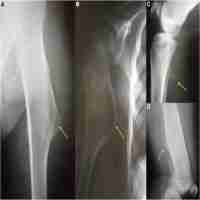

| Abstract | Multiple osteochondromas (also called hereditary multiple exostoses) is an autosomal dominant disorder characterized by multiple cartilaginous tumors, which are caused by mutations in the genes for exostosin-1 (EXT1) and exostosin-2 (EXT2). The goal of this study was to elucidate the genetic alterations in a family with three affected members. Isolation of RNA from the patients’ blood followed by reverse transcription and PCR amplification of selected fragments showed that the three patients lack a specific region of 90 bp from their EXT1 mRNA. This region corresponds to the sequence of exon 8 from the EXT1 gene. No splice site mutation was found around exon 8. However, long-range PCR amplification of the region from intron 7 to intron 8 indicated that the three patients contain a deletion of 4318 bp, which includes exon 8 and part of the flanking introns. There is evidence that the deletion was caused by non-homologous end joining because the breakpoints are not located within a repetitive element, but contain multiple copies of the deletion hotspot sequence TGRRKM. Exon 8 encodes part of the active site of the EXT1 enzyme, including the DXD signature of all UDP-sugar glycosyltransferases. It is conceivable that the mutant protein exerts a dominant negative effect on the activity of the EXT glycosyltransferase since it might interact with normal copies of the enzyme to form an inactive hetero-oligomeric complex. We suggest that sequencing of RNA might be superior to exome sequencing to detect short deletions of a single exon. |